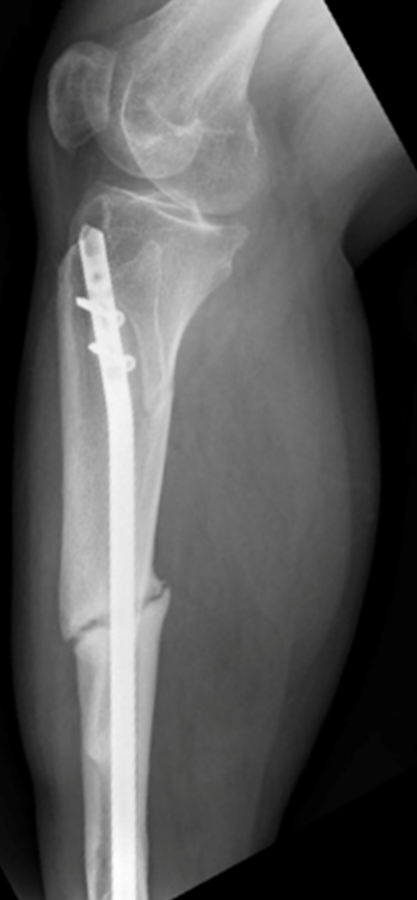

Both mechanical and biological factors influence how a bone heals. Mechanical factors—such as the rigidity of the implant meant to stabilize the fracture, the distance between bone ends, and the loading pattern on the limb—have been studied for decades, says Dailey, and existing models show how these physical and structural conditions set the stage for healing. Less well understood, however, are the biological factors—the cellular, molecular, and systemic processes that actually rebuild the bone.

Another innovative aspect of the project is the team’s plan to add their model to ARI’s online training platform OSapp. As one of the world’s premier organizations for surgeon education, ARI supports interactive simulations available to professionals around the world. The modules provide instruction on topics including instrumentation; manipulating implants, such as plates and screws, and determining their proper length and number; and discussing recovery options with patients.

“We all know that biology is really hard to control, but surgeons can control mechanics,” says Dailey. “For example, they can change the way they use implants or what they tell a patient about how to rehab. Our model will help them visualize how those mechanics can change the biological response.”